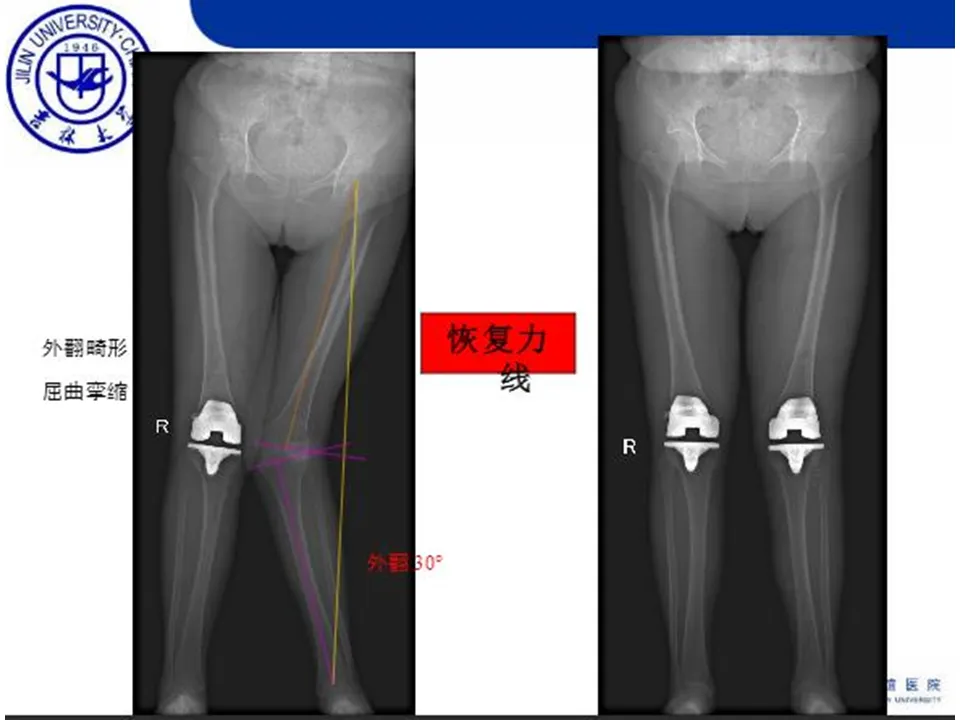

>【骨科PPT】全膝关节置换的截骨原则

【骨科PPT】全膝关节置换的截骨原则